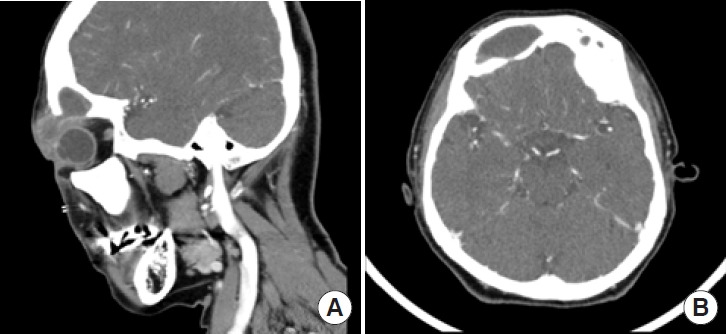

一位76岁的妇女最初被认为是右上眼睑单纯脓肿,后来到我院整形外科就诊。增强面部三维计算机断层扫描(CT)显示右上眼睑有脓肿,右额窦有脓肿,右眼眶上壁伴有骨侵蚀。根据 CT 扫描的结果,我们诊断为非典型 Pott's 膨出瘤(PPT),上睑脓肿源于额窦炎。首先,我们在科室进行了手术切开引流,并放置了经皮真空引流管。为了提供更确切的治疗,耳鼻喉科医生随后为患者实施了内窥镜鼻窦手术(ESS)。ESS术后5天,患者顺利出院,未出现任何并发症。在 1 年的随访中,没有发现复发或明显的神经症状。在我们观察到的病例中,患者出现了上眼睑脓肿和蜂窝组织炎,表明可能累及眼眶。对于这类患者,有必要进行 CT 扫描。考虑到 PPT 的可能性,关键是要进行全面的鉴别诊断,而不是直接采用治疗脓肿的方法。

A 76-year-old woman, initially thought to have a simple abscess on her right upper eyelid, presented to our department of plastic and reconstructive surgery. Enhanced three-dimensional facial computed tomography (CT) revealed an abscess on the right upper lid, with a pyomucocele present in the right frontal sinus, accompanied by bone erosion in the superior wall of the right orbit. Based on the results of the CT scan, we diagnosed an atypical Pott's puffy tumor (PPT) with an abscess on the upper lid originating from the frontal sinusitis. First, surgical incision and drainage were performed in our department, and a percutaneous vacuum drain was placed. To provide a more definitive treatment, endoscopic sinus surgery (ESS) was subsequently performed by otorhinolaryngologists. The patient was discharged without any complications 5 days after ESS. At a 1-year follow-up, no recurrence or notable neurological symptoms were observed. In the case we observed, the patient presented with an upper eyelid abscess and cellulitis, indicating possible orbital involvement. For such patients, a CT scan is necessary. Given the possibility of PPT, it is critical to perform a comprehensive differential diagnosis rather than defaulting to a straightforward approach involving abscess treatment.